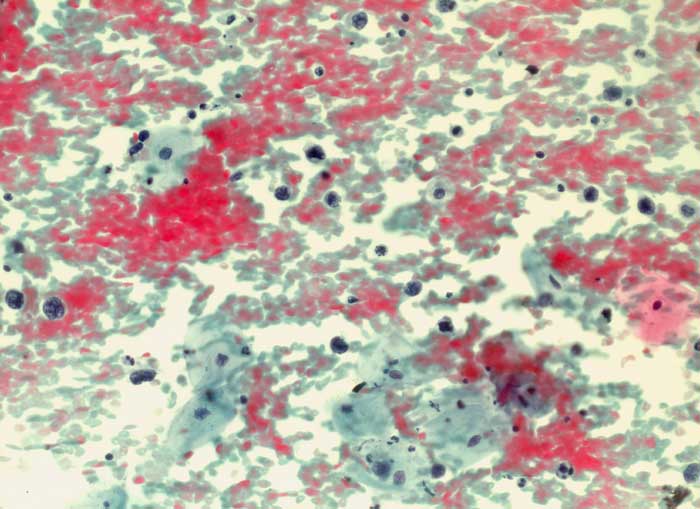

Diffuses grosszelliges B-Zell Lymphom der Zervix

Maligne Lymphome der Zervix sind selten. Meist handelt es sich um die Manifestation eines generalisierten Lymphoms in der Zervix und nicht um ein primäres Zervixlymphom. Beim diffusen grosszelligen B-Zell Lymphom lassen sich einzeln liegende atypische blastäre Zellen nachweisen, die mindestens zweimal so gross sind wie kleine Lymphozyten. Die Kerne sind vesikulär und enthalten einen solitären zentralen oder mehrere periphere Nukleolen. Ausserdem sind Apoptosen, kleine Lymphozyten, Plasmazellen und Makrophagen zu sehen. Der Ausstrichhintergrund enthält oft Detritus.